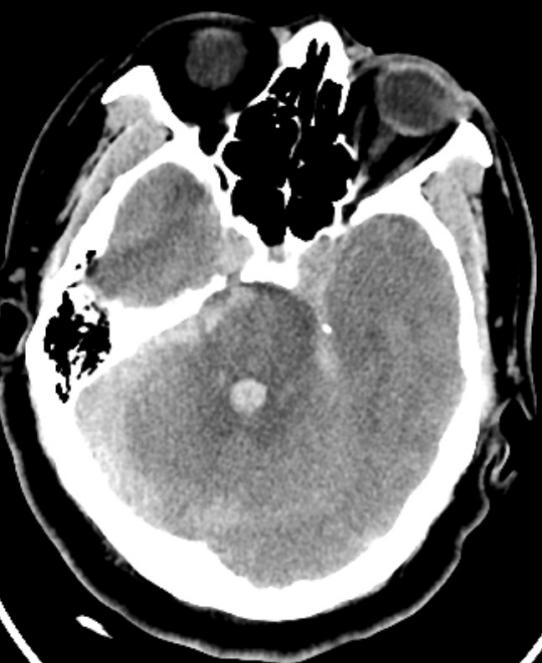

患者韩先生,入院3天前洗澡后出现头痛头晕,未诊治,因症状加重前来清华大学附属垂杨柳医院神经内科门诊就诊。期间,患者头痛剧烈,伴恶心呕吐,被紧急送至急诊科,头颅CT提示蛛网膜下腔出血、脑室出血(Fisher分级4级)。随即患者出现昏迷,GCS5分,呼吸困难,急诊行气管插管,呼吸机辅助呼吸,并联系医院神经外科前来急会诊。

▲头颅CT显示广泛蛛网膜下腔出血,脑室积血